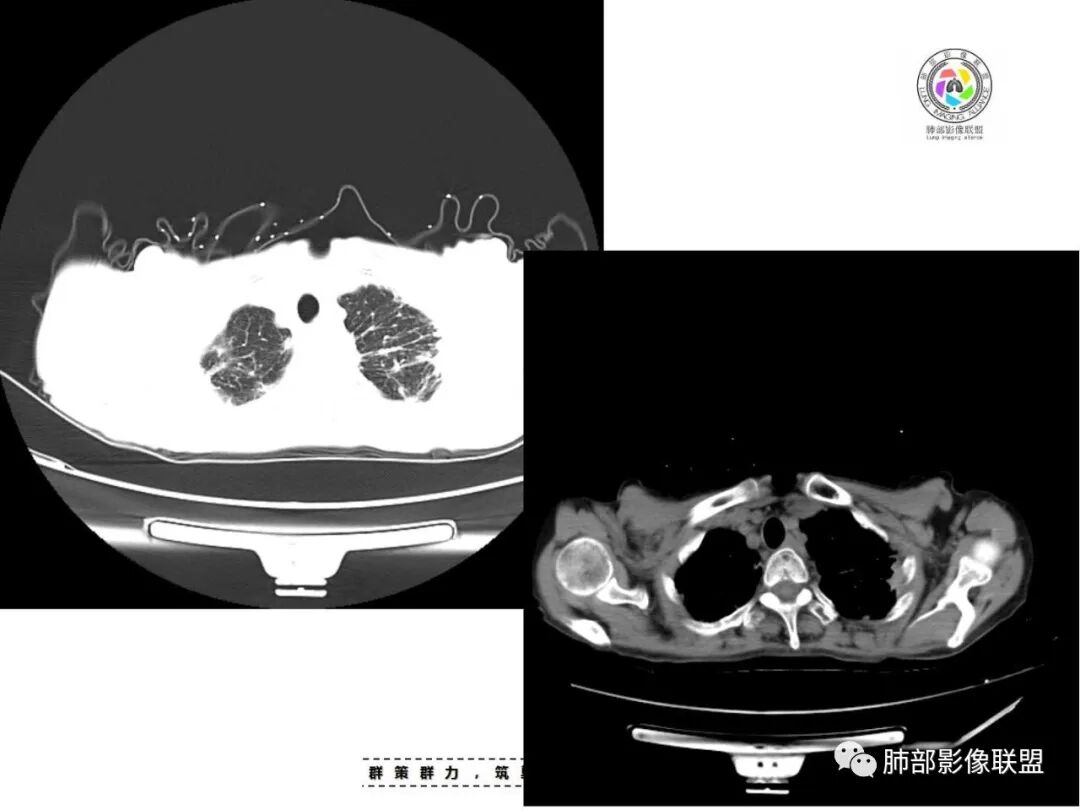

老年女性,67岁,咳嗽、咳痰半月余。双肺可闻及痰鸣音。

胸部CT:双肺上叶多发小结节,沿胸膜下、支气管血管束分布。右上肺斑片实变影、索条影及小叶间隔不均匀增厚,支气管枯枝征?纵隔淋巴结多发肿大,部分有钙化。综合考虑:结节病?尘肺?鉴别:腺癌并癌淋。

1.双肺片状影、大小不等斑片影、结节影、树芽等,病灶密度偏高多钙化。

2.病灶上肺为主,胸膜下分布为主。双肺病灶明显不对称,右肺块状影较大。

3.纤维条索影广泛杂乱、牵拉,横向分布为主,这点给人也印象很深!

4.纵隔轻度右移。双肺门纵隔淋巴结增大钙化。

5.老年女性患者,咳嗽咳痰半月余